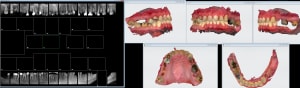

Mise en charge immédiate en 1 seul temps chirurgical avec le protocole Positdental.jpg

0A49BEBE-5EBF-4385-8CD2-B8EF582DCB11.jpg